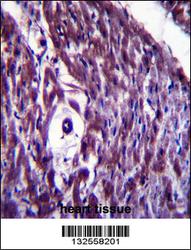

Supportive validation

- Submitted by

- Aviva Systems Biology (provider)

- Main image

- Experimental details

- MAGED4B Antibody (Center) (Cat. #OAAB09741)immunohistochemistry analysis in formalin fixed and paraffin embedded human heart tissue followed by peroxidase conjugation of the secondary antibody and DAB staining.This data demonstrates the use of MAGED4B Antibody (Center) for immunohistochemistry. Clinical relevance has not been evaluated.